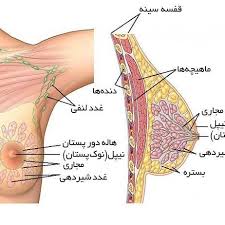

قیمت: 68٬000 تومان - دسته بندی فایل: پاورپوینتپاورپوینت بیماریهای پستان

فروش ویژه پاوزپوینت حرفه ای بیماریهای پستان با تخفیف استثنایی قیمت 86 هزار تومان تعداد اسلاید: 39 اسلاید